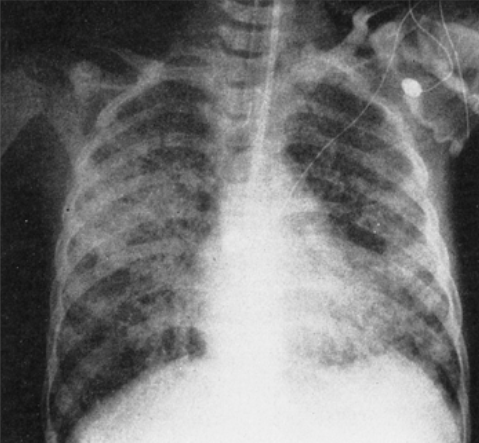

What parasite causes the lesions shown below in the GI tract? What other complications can arise form this infection?

Note the “flask-shaped” ulcer, typical of entamoeba histolytica. It gets to the liver via the splanchnic vessels and causes abscesses. Liver abscesses can also break through the diaphragm and enter the pleural space.